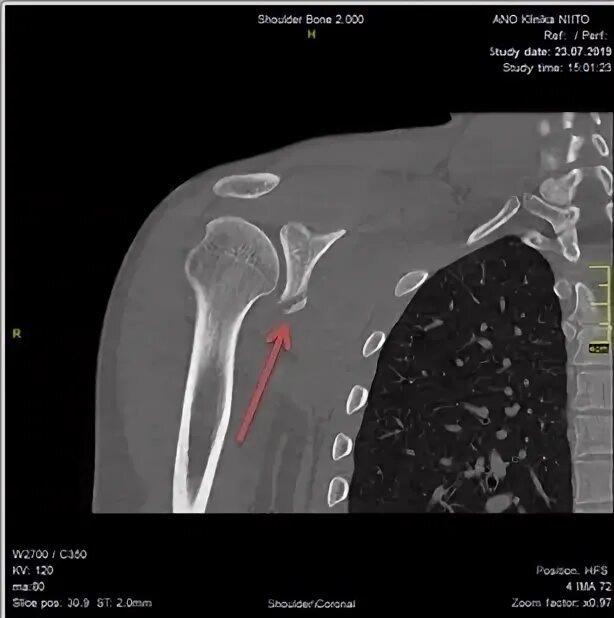

Нестабильность плечевого сустава мкб